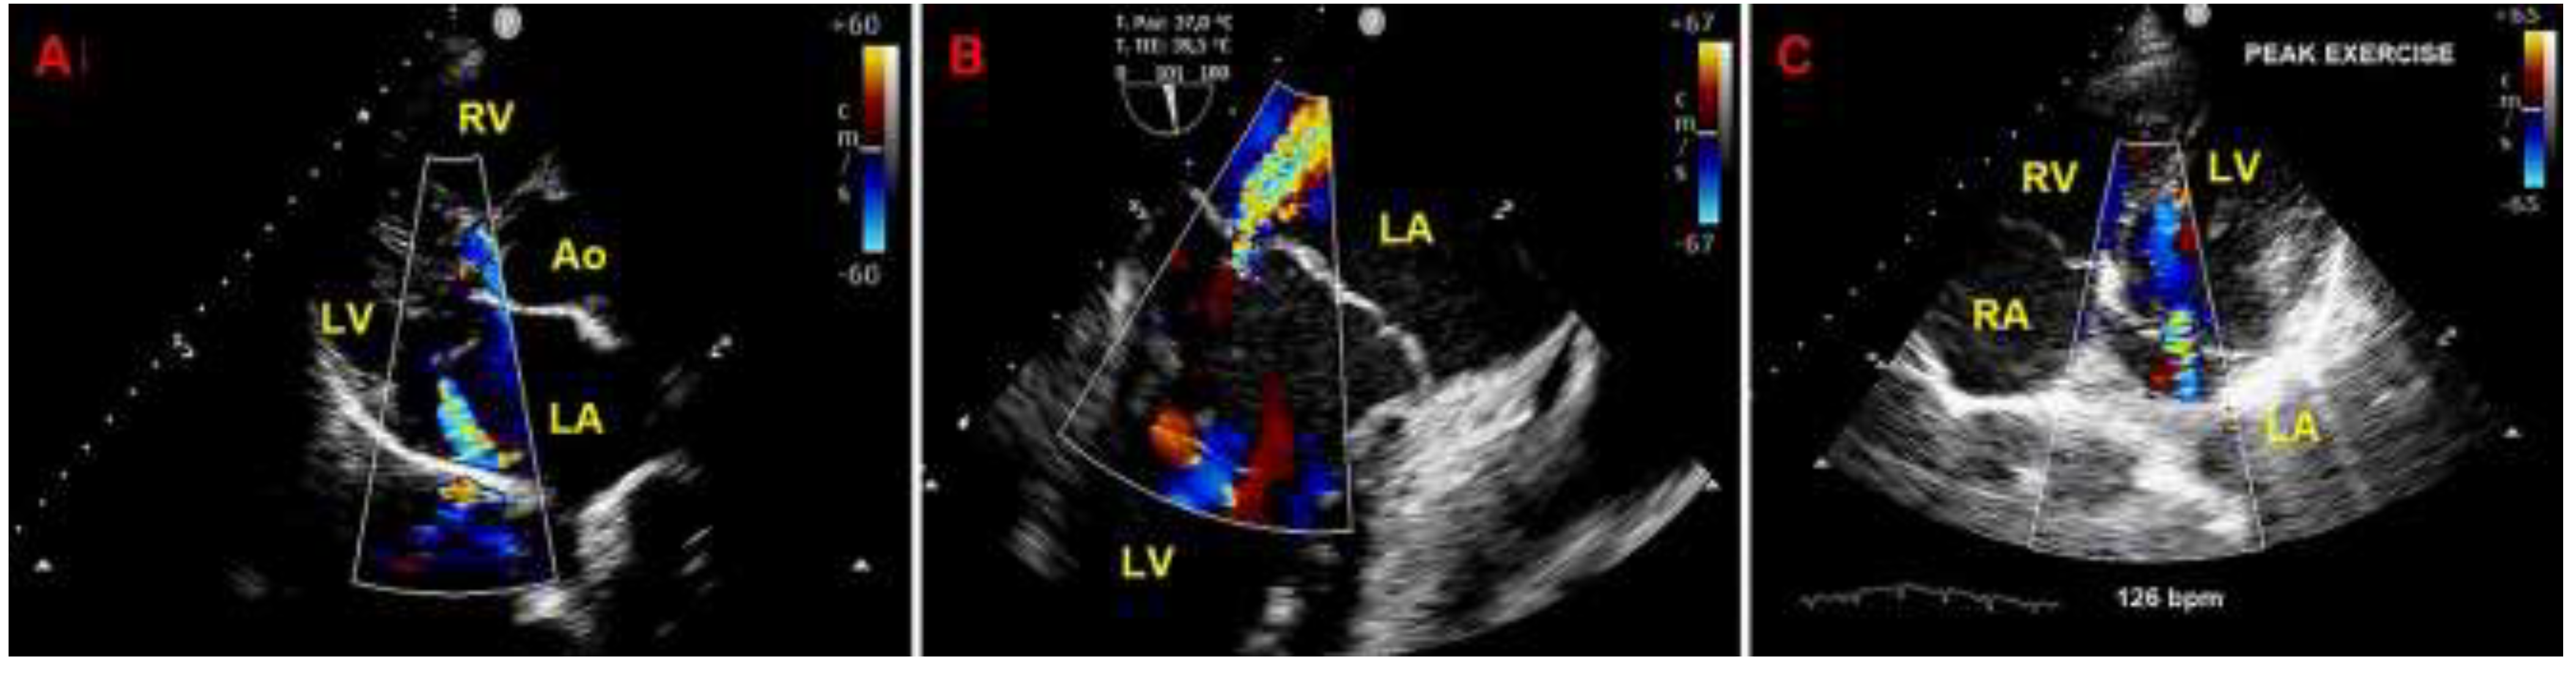

Given that the patient was symptomatic for exercise-induced dyspnea and that we detected a moderate MR due to MVP on both TTE and TEE, she underwent also ESE. On ESE, the patient performed a maximal physical exercise (by achieving 85% of maximal age predicted heart rate), the moderate MR did not show any significant modification in comparison to resting conditions (Figure 7), the pulmonary hemodynamics was normal (estimated peak exercise sPAP = 45 mmHg), the patient showed a good exercise tolerance and did not manifest palpitations.

Figure 7. Moderate mitral regurgitation detected on resting transthoracic echocardiography from the parasternal long-axis view (A), on transesophageal echocardiography from the bicommissural view (B) and on exercise stress echocardiography from the apical four-chamber view recorded at peak exercise (C). Ao, aorta; LA; left atrium; LV, left ventricle; RA, right atrium; RV, right ventricle.